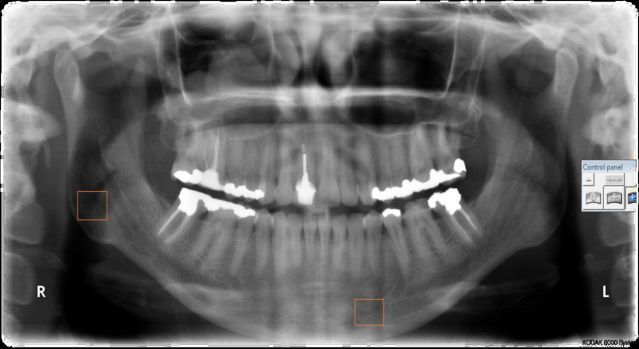

Objectives: The aim of the study was to assess the efficacy of digital panoramic radiographs as a triage screening tool for osteoporotic changes in a large population. It is an attempt to identify the role dentists may play, as part of the medical fraternity, in early detection and and prompt referral of potential cases of osteoporosis for further medical investigations.

Methods: Evaluation of digital orthopantomograms of 3 groups of female patients that is groups A, B, and C based on their age thats is 20-40 years, 40-60 years and ≧60 years respectively. 3 radiographic indices recorded for each of these films namely the Panoramic mandibular index (PMI), Mandibular cortical width (MCW), and Pixel intensity (PI) using Image J software (1.48v) and assessed for changes in value of each index with increasing age of the patient.A comparison was sought between the two morphometric indices (PMI, MCW) and the Pixel intensity index (PI).

Conclusions: Evaluation of radiographic indices from routinely done digital orthopantomograms can provide useful preliminary information about a patient's risk for developing osteoporosis and be used for triage screening and referral of suspected cases without incurring any additional costs. This study also suggested age to be an important risk parameter for osteoporosis.